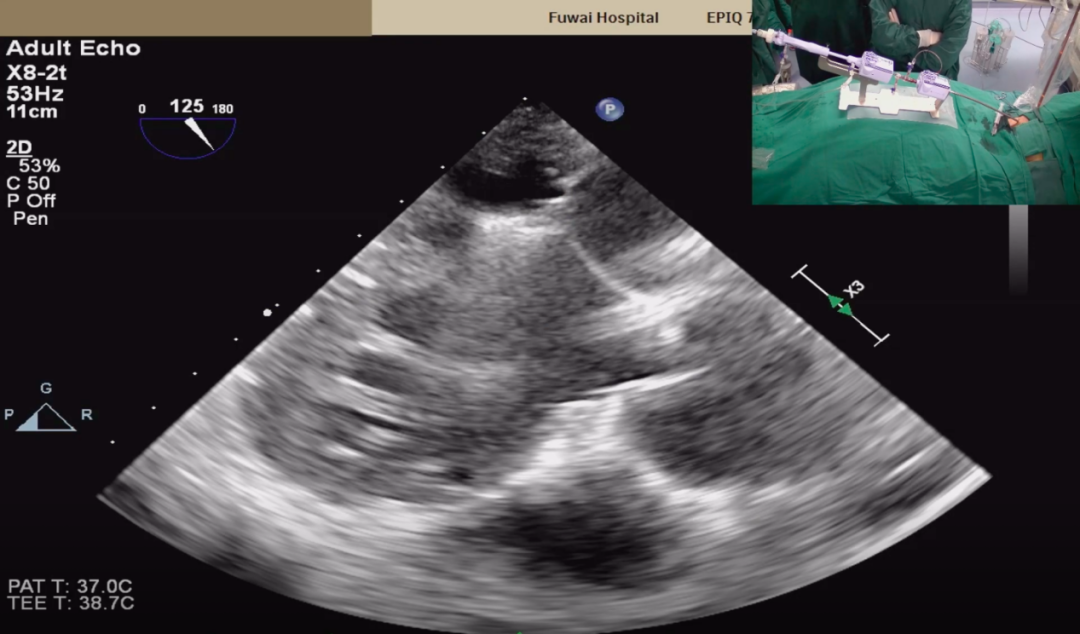

穿刺后将导管送入左心房,靠近二尖瓣目标位置。术中发生了最令人担心的输送系统头端缠绕了腱索,经仔细调整输送系统,解除腱索缠绕后再次靠近二尖瓣二区的位置,准确捕获二尖瓣瓣叶。初次夹闭时二尖瓣后瓣夹闭部分较少,松开瓣夹后再次调整位置,准确捕获并充分夹闭二尖瓣瓣叶,完成经导管缘对缘修复。

超声确定二尖瓣夹夹闭位置